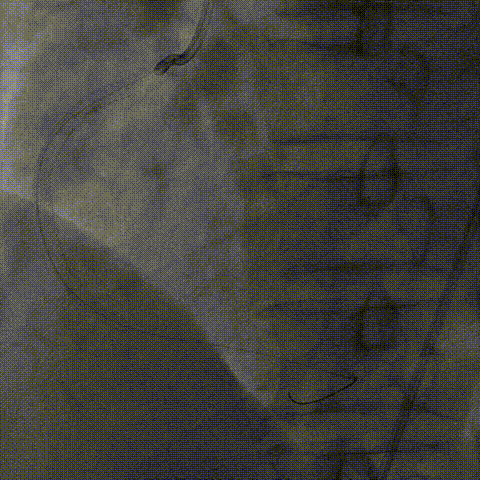

器械通过困难:

1、2.0mm顺应性球囊预扩后,Telescope™支撑下火山血管内超声(头端直径较大)无法通过,操作过程中右冠系统脱出,重新放置右冠指引管后在逆向导丝指引下正向导丝再次通过病变至右冠远端。

2、换用2.75非顺应性球囊在Telescope™支撑下扩张闭塞段并引导Telescope™通过闭塞段后完成血管内超声检查。

内腔同时兼容2.0mm球囊及Finecross微导管

介入经过及结果

血管内超声:

导丝远端位于血管真腔,闭塞段部分内膜下走行,可见闭塞段钙化,符合术前评估结果。